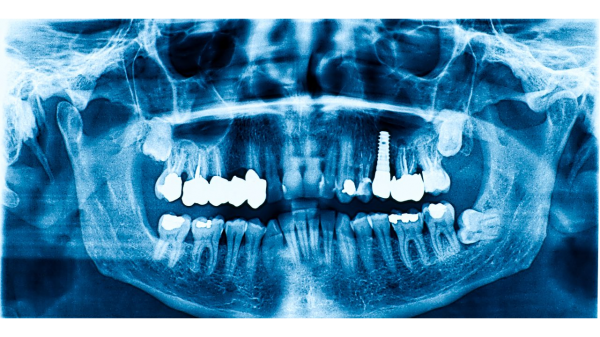

-- Valleant has published a new article titled "Are Dental X-Rays Safe: Understanding the Risks and Benefits," which explores the essential aspects of dental X-rays for various audiences, including patients, parents and guardians, dental professionals, health educators, students in dental and health programs, and health-conscious individuals. The article serves as a valuable resource for anyone seeking to understand the necessity, safety, and potential risks of dental X-rays before undergoing procedures.

One particularly interesting fact highlighted in the article is that advancements in dental imaging technology, such as digital X-rays, have significantly reduced radiation exposure compared to traditional film X-rays. Digital X-rays can lower radiation doses by up to 80%, making them a safer option for both patients and dental professionals. This innovation not only enhances patient safety but also improves image quality, leading to more accurate diagnoses and better treatment planning. Other interested individuals can view the full article at https://valleant.com/are-dental-x-rays-safe/

An important extract from the article emphasizes that while dental X-rays involve exposure to a small amount of ionizing radiation, advancements in technology, such as digital X-rays, have significantly reduced this exposure. The article underscores that the benefits of dental X-rays—such as early detection of cavities, gum disease, and other oral health issues—are crucial for effective treatment and overall dental health.